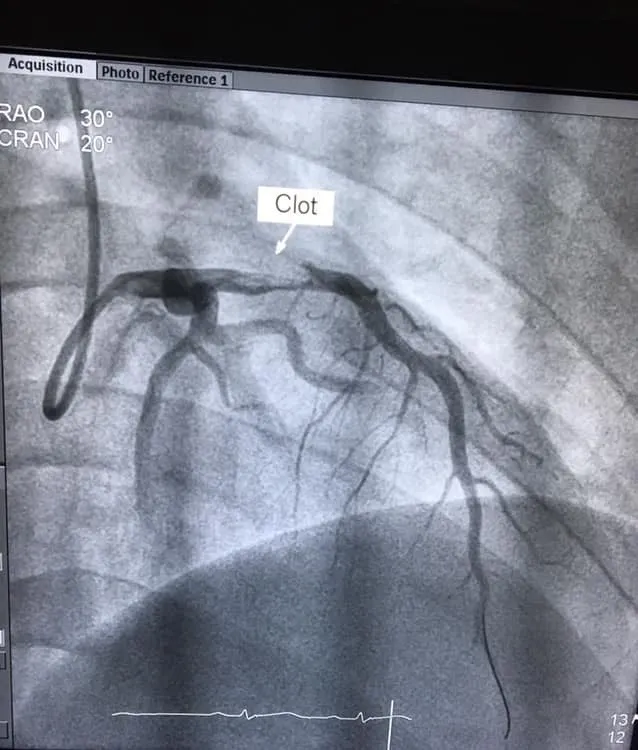

ผู้ป่วยชาย อายุ 23ปี สูบบุหรี่

แน่นหน้าอก 15นาที ก่อนมาโรงพยาบาล

ฉีดสีหลอดเลือดหัวใจพบลิ่มเลือดอุดตันหลอดเลือดด้านซ้าย ได้รับการทำบอลลูนใส่ขดลวด